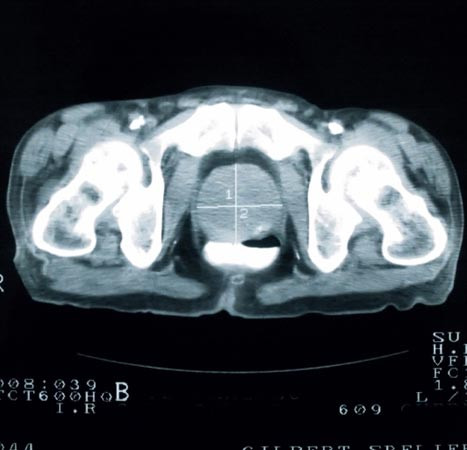

Ung thư tuyến tiền liệt chỉ gặp ở nam giới - đặc biệt là những người trên 50 tuổi. Tiến hành kiểm tra tuyến tiền liệt thường xuyên là điều bắt buộc với nam giới tuổi trung niên để tránh căn bệnh chết người này.